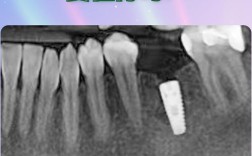

种植牙的核心原理是将人工种植体(纯钛或钛合金)植入牙槽骨内,通过骨结合(osseointegration)与骨组织融合,形成类似“人工牙根”的结构,牙槽骨的骨量(高度、宽度、厚度)和骨密度直接影响种植成功率。

牙槽骨骨量充足:理想情况下,缺牙区牙槽骨高度需>10mm,宽度>5mm,密度为Ⅲ-Ⅳ类(骨皮质与骨松质比例适中),此时可直接植入种植体,手术创伤小,愈合快。

牙槽骨骨量不足:牙齿缺失后,牙槽骨会因失去咀嚼刺激而逐渐萎缩,尤其是缺牙后3-6个月是快速吸收期,若骨量不足,需先进行骨增量手术,如: